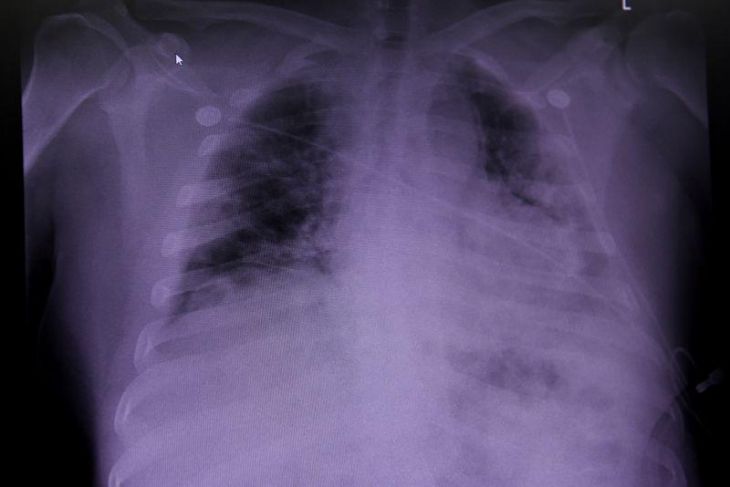

Foto: Reuters

Un equipo del Instituto de Salud Carlos III (ISCIII) y de varias áreas del Centro de Investigación Biomédica en Red (Ciber) describen un nuevo modelo para estudiar el neumococo, la bacteria causante de enfermedades como la neumonía y la meningitis, gracias al desarrollo de organoides pulmonares, es decir, de mini pulmones generados en laboratorio con células pluripotentes embrionarias que imitan la actividad de los pulmones reales.

El neumococo es una bacteria que puede producir enfermedades leves, como otitis y sinusitis, pero también otras graves, como neumonías, meningitis y sepsis, siendo los niños menores de cinco años y las personas mayores de 65 años los más vulnerables a estas infecciones.

Así pues, el modelo de estudio basado en mini pulmones derivados de células troncales pluripotentes embrionarias humanas permite analizar cómo se comporta el neumococo en estos organoides artificiales, permitiendo a los investigadores comprender mejor su comportamiento cuando infectan pulmones reales.